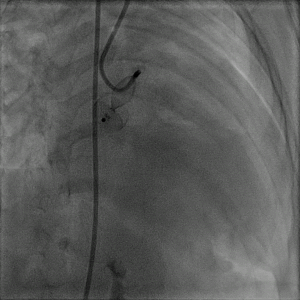

术后造影示栓塞处少量穿伞分流,前降支通畅,冠状静脉窦通畅。

图片